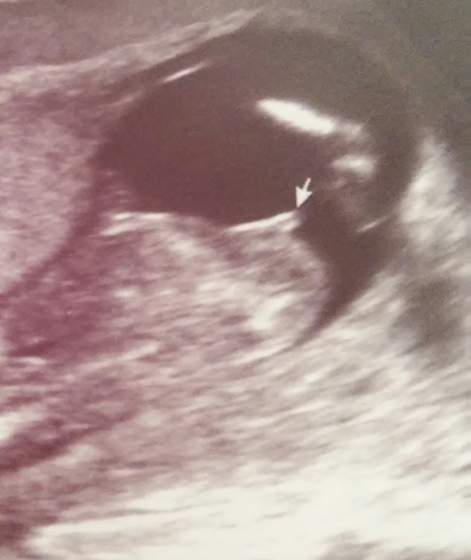

rsz jak dla mnie ewidentnie dziewczynka nub jest plaski to co wystaje miedzy nozkami to wlasnie nub (wyrostek plciowy) ulozony jest plasko jezeli bylby uniesiony no to chlopiec ale u Ciebie widac ze jest plasko

Magic 87 , znalazłam takie zdjęcie w internecie i to był chłopczyk a nub wydaje się być ułożony płasko 7fc6f57926a5f187f915dcc9f68a9c3e.jpg

rsz dla mnie tez plaski a moze pomylka na stronie? a moze te 20% to wlasnie takie przypadki, roznie bywa mojej kolezance do 6m mowili rozni lekarze ze chlopczyk a urodzila coreczke takze bardzo zadko ale sie zdarza tu na forum to jest az niemozliwe ze tyle dziewczyn to dotyczy:-)